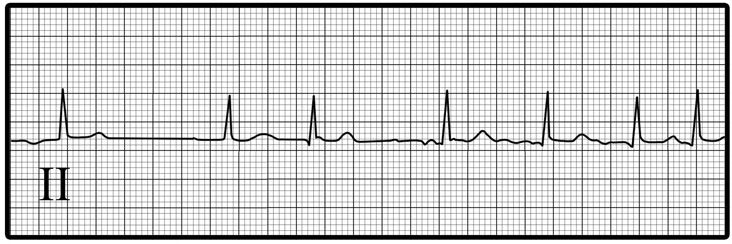

Rhythm strip

It was obtained during an episode of palpitations.

Choose the best interpretation of the rhythm strip:

Multifocal atrial tachycardia

Atrial flutter

Atrial fibrillation

Sinus tachycardia

Sinus rhythm with

premature atrial complexes